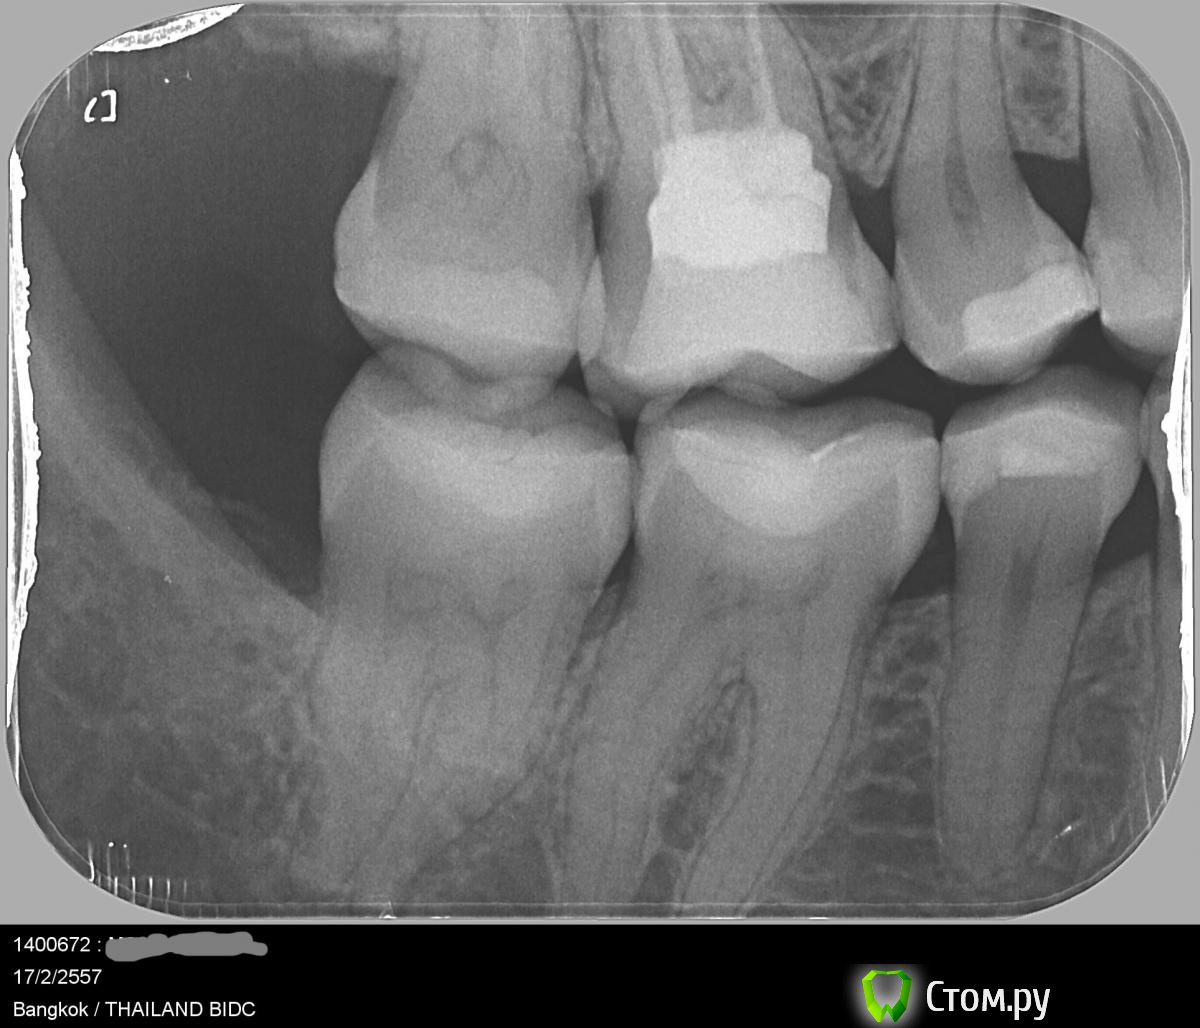

diesel87 Опубликовано 17 февраля, 2014 Поделиться Опубликовано 17 февраля, 2014 Здравствуйте, по снимку самое интересное не видно, верхушки корней. Видна только пломба близко к полости с нервами, а помимо того что он периодически ноет что еще беспокоит? Реакция на холодное или сладкое, боль при накусывании или самопроизвольные боли? Еще возможно есть карман между 5 и 6 зубами, есть не приятный запах? Ссылка на комментарий

diesel87 Опубликовано 18 февраля, 2014 Поделиться Опубликовано 18 февраля, 2014 немного похоже на простреливающую, но она не острая, не сосредоточенная, а как будто общая ноющая боль вдруг стала сильной во весь зуб.Ничего конкретного после подобного общения сказать не могу и не имея снимка верхушек корней, но мне кажется дело в глубоко или поставленной не по протоколу пломбе. Ссылка на комментарий